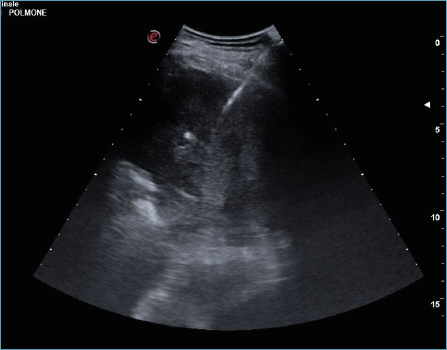

L’uso clinico dell’ecografia, iniziato negli anni ’60, ha conosciuto un progressivo sviluppo nelle applicazioni diagnostiche e terapeutiche, tanto in ambito clinico quanto radiologico. In Pneumologia, l’ecografia toracica è ormai una tecnica consolidata, considerata complementare all’esame obiettivo tradizionale. Questa metodica è impiegata nello studio dei versamenti pleurici e nelle procedure a essi correlate (toracentesi, posizionamento di drenaggi, etc.), ma è negli ultimi anni che gli ultrasuoni sono stati adottati anche per l’analisi di masse pleuriche, polmonari e della parete toracica, in particolare per l’esecuzione delle biopsie. La possibilità di ottenere biopsie adeguate (con una sensibilità del 73% e una specificità del 100%) 1 consente una diagnosi più accurata, fornendo materiale sufficiente per le successive terapie oncologiche, superando così i limiti legati all’analisi del solo liquido pleurico e, talvolta, all’impossibilità di eseguire una toracoscopia a causa delle condizioni cliniche del paziente 2,3. Rispetto alle biopsie TC-guidate, quelle eco-guidate presentano alcuni vantaggi: sono infatti eseguibili al letto del paziente, offrono una visione in tempo reale della lesione da campionare in relazione al respiro del paziente e non comportano l’uso di radiazioni ionizzanti. Uno dei limiti consiste nel fatto che si tratta di una tecnica “operatore-dipendente” 4. Di seguito desideriamo condividere l’esperienza della nostra Unità di Pneumologia nella gestione delle lesioni tramite l’agobiopsia transtoracica eco-guidata (US-TTNB) eseguita direttamente dallo pneumologo (Fig. 1).

Figura 1.Visione ecografica di lesione polmonare adesa alla pleura compatibile con adenocarcinoma polmonare con ago da biopsia al suo interno.